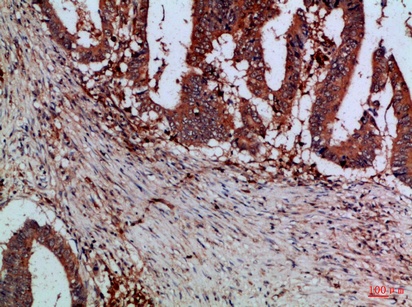

Fig.2. Immunohistochemical analysis of paraffin-embedded Human-colon-cancer, antibody was diluted at 1:100.